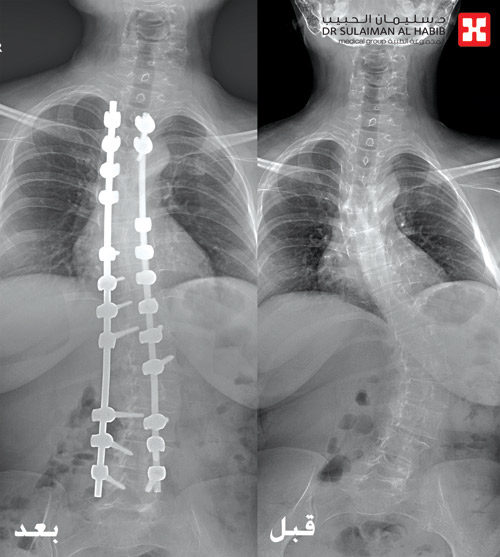

تمكن مستشفى الدكتور سليمان الحبيب بالريان، من إنهاء معاناة سيدة تبلغ من العمر «35» عاماً، مع جنف حاد بالعمود الفقري يقدر بـ 60 درجة، ونجح الفريق الطبي المعالج بقيادة الدكتور بندر السبيعي استشاري جراحة العظام والعمود الفقري، في إجراء عملية معقدة استمرت 6 ساعات لتقويم العمود الفقري، وتثبيت ودمج الفقرات دون أية مضاعفات ولله الحمد.

وأضاف أن الفحوصات أظهرت وجود انحراف في العمود الفقري بنسبة 60 درجة، وبعد دراسة كافة نتائج الفحوصات، قرر الفريق التدخل جراحياً لعلاج الحالة. وقد أجرى الفريق العملية للسيدة واستخدم فيها تقنية رصد ومراقبة الإشارات العصبية أثناء العمل الجراحي (Intraoperative Neuromonitoring)، وذلك للاطمئنان على سلامة الحبل الشوكي والأعصاب، كما تم استخدام سرير خاص بغرفه العمليات «Jackson table» للحصول على أفضل النتائج العلاجية، ونقلت بعدها المريضة إلى جناح التنويم.

وأضاف د. السبيعي أن الفحوصات الأولية بعد العملية أشارت إلى استقرار وتحسن حالة المريضة الصحية، وقد استطاعت الوقوف والمشي في اليوم الثاني بمساعدة أخصائي العلاج الطبيعي، وخرجت من المستشفى بعد 5 أيام، وهي بصحة جيدة بعد التأكد من انتهاء كافة نوبات الألم، كما أنها عادت لممارسة حياتها بصورة طبيعية.